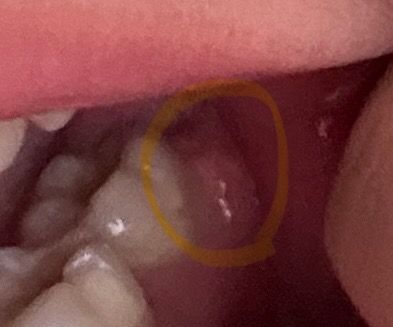

젤 안쪽 어금니 옆에 잇몸이 어제아침부터 저렇게 부어서 닿을때마다 아픈데요ㅜㅜ 사랑니 나는 건가요? 사랑니가 저 위치에도 나요?.... 어금니 뒤에 나는 게 사랑니 아니에효ㅠㅠ???

• 1번 째 사진

사랑니로 인한 증상일 수 있어 보입니다. 하지만 지금의 사진만으로는 정확한 판단이 어렵습니다. 통증이나 불편감이 나타났고 사랑니 부위이므로 가까운 치과 방문 후 x-ray 등을 촬영하여 평가를 받아보는 것이 필요해보입니다.

어금니는 2개있고 세번째 어금니가 사랑니입니다 사진상 보이는 2개의 어금니가 제1,2대구치라면 잇몸 안쪽으로 사랑니가 나고 있을 수 있고, 옆에가 사랑니라면 제4대구치(두번째 사랑니)가 있는 것일 수도 있습니다